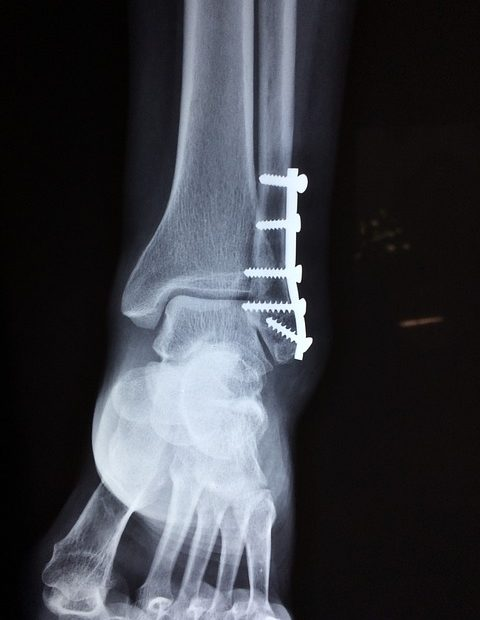

The problem with grade 3 sprains is that they can be accompanied by more serious fractures and other complications.

If you do something severe enough to tear a ligament, this force may be enough to cause more damage in the area:

For this reason, it's really a good idea to see a doctor - they have the necessary expertise and tools to give you a full diagnosis and make sure nothing too sinister is happening beneath the surface.